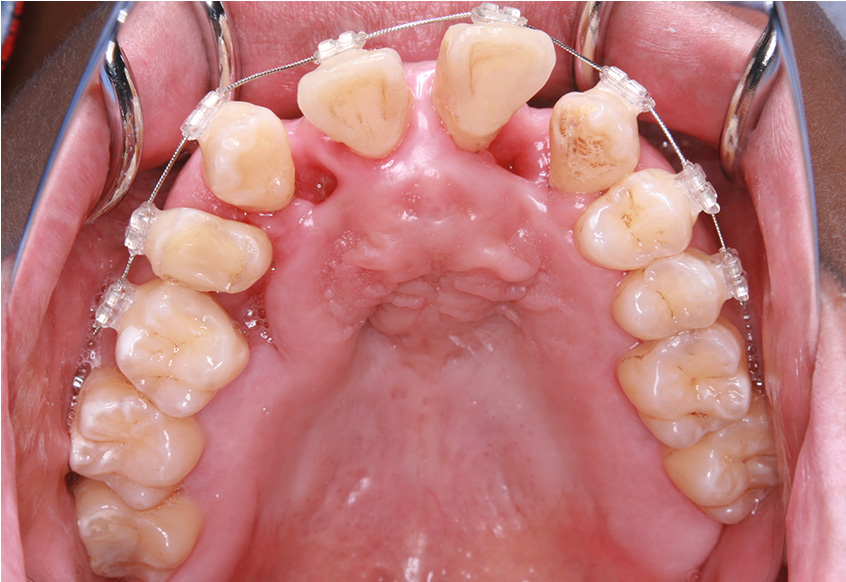

最初のお口の中 ワイヤー装着して治療を開始

-